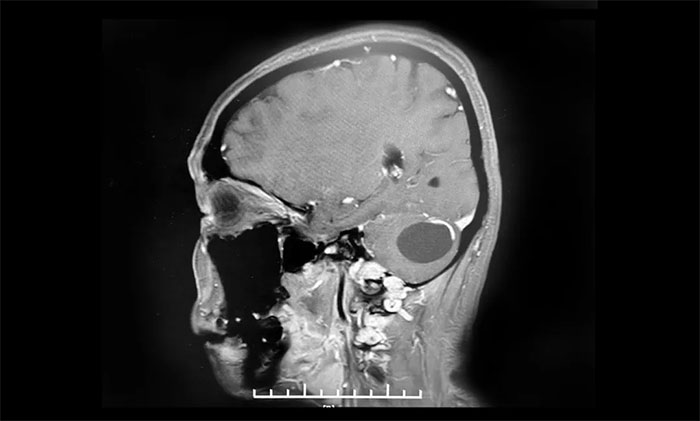

6个月前,小妍在无任何诱因的情况下出现了头晕,一旦发作就觉得天旋地转,2月前在头晕发作时还会出现枕部头疼,10余天前又出现了行走时步态不稳症状。小妍的母亲赶紧将小妍带到了当地医院检查,经行头颅MRI显示,在小妍的左侧小脑半球有一长T1长T2圆形囊实混合占位,大小约4.2*3.2cm,考虑为“脑血管母细胞瘤”,并且合并脑积水,建议其手术治疗。

▲ 右侧小脑血管母细胞瘤,大小约34x34mm